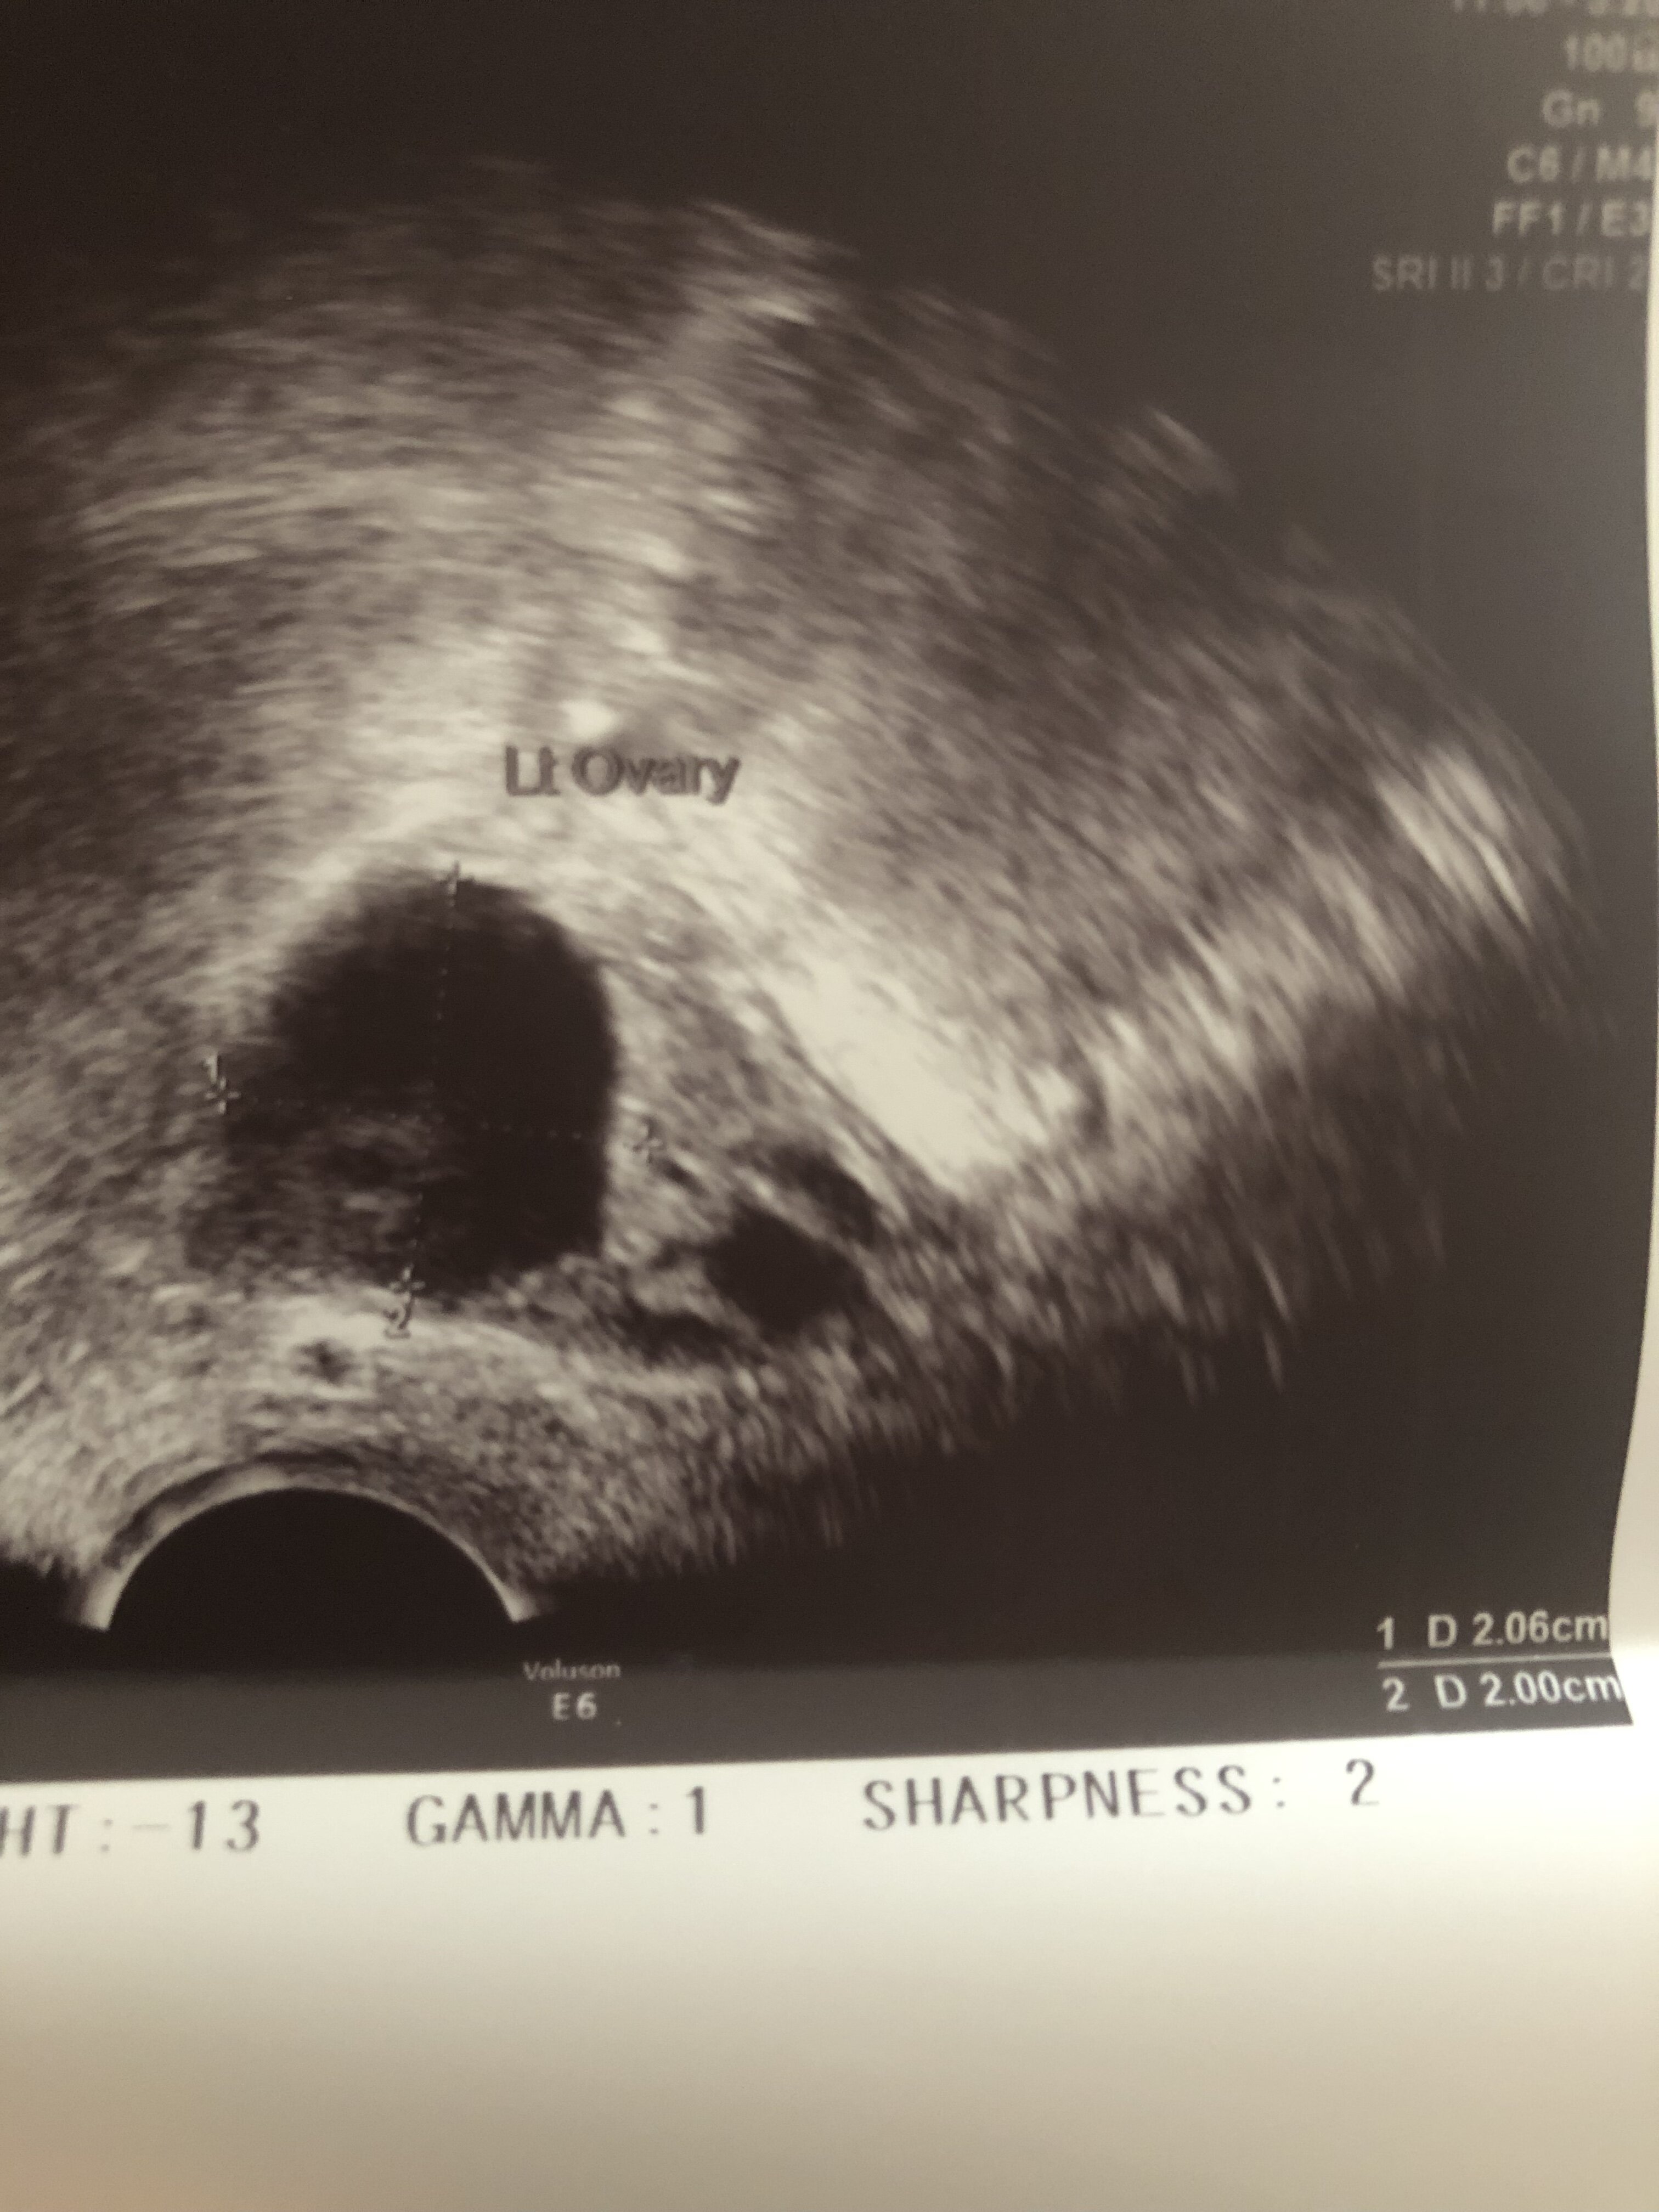

W którym miejscu na zdjęciu będzie to endometrium? To będzie to ze zdjęcia 0,75? Takie miałam w 14dc w 15 owu a w 16 0,92 jeśli dobrze odczytuje.A co masz na opisie? Powinnaś mieć grubość endometrium, wielkość jajników i wielkość pęcherzyków dominujących przynajmniej w 2 wymiarach.

A pokaż całość zdjęcia z tym wymiarem 0,75 bo ucięłaś połowę. To może być oczywiście endometrium.W którym miejscu na zdjęciu będzie to endometrium? To będzie to ze zdjęcia 0,75? Takie miałam w 14dc w 15 owu a w 16 0,92 jeśli dobrze odczytuje.

Wrzucam akurat z dnia po owu 0,92 jest o ile coś widaćA pokaż całość zdjęcia z tym wymiarem 0,75 bo ucięłaś połowę. To może być oczywiście endometrium.

Szczerze Ci powiem pierwszy raz widzę taki obraz endometrium, więc nie mam bladego pojęcia czy to to. Ale z drugiej strony nie jest to ani jajnik ani nic innego. Szkoda że nie dostałaś opisuWrzucam akurat z dnia po owu 0,92 jest o ile coś widać![]()